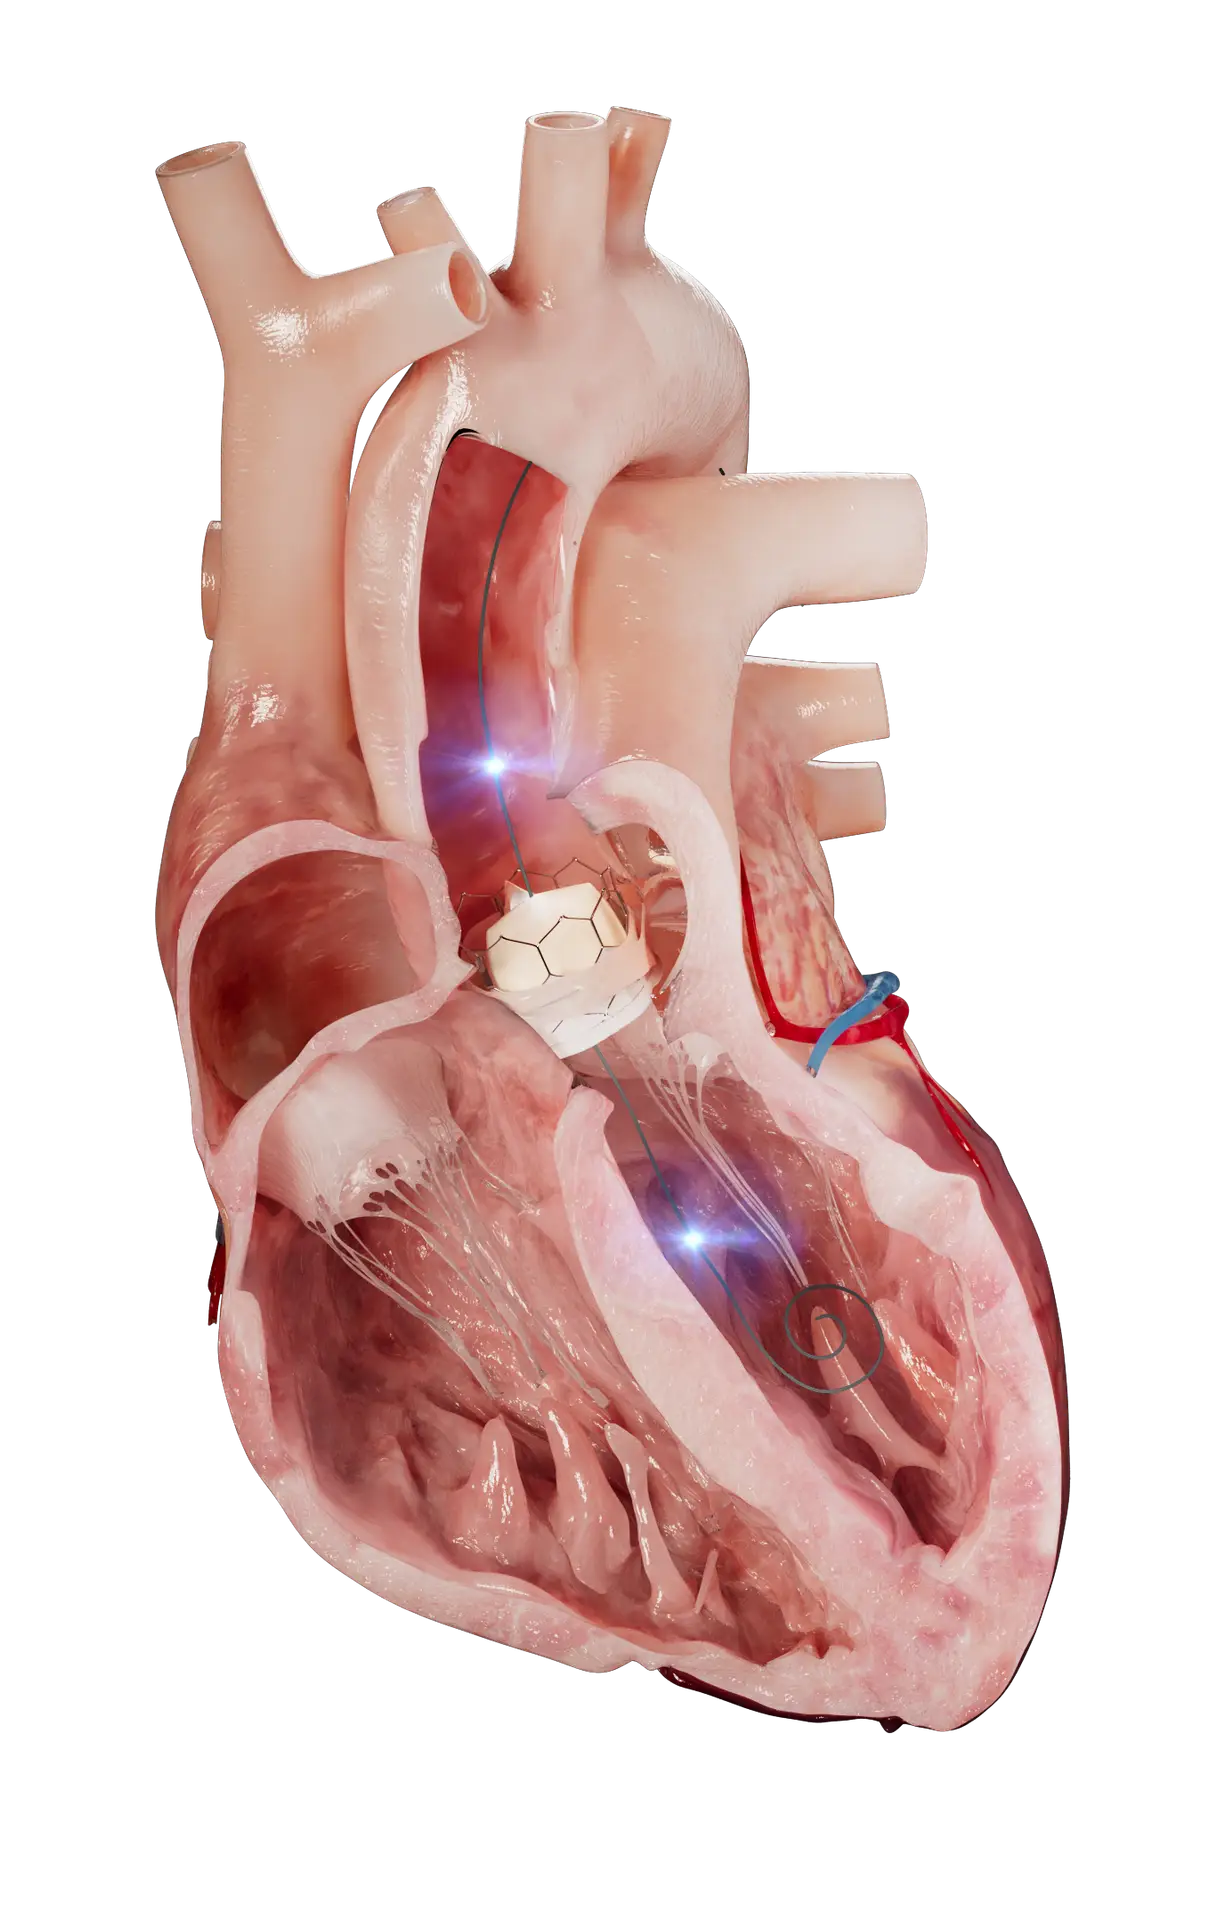

Xenter is infusing novel technologies into workhorse medical devices

Xenter devices gather Physical Intelligence and wirelessly transmit the data through the XenFi™ system and into the XMD™ global healthcare cloud. This foundation unlocks precise and powerful Artificial Intelligence in the clinical world, empowering providers and improving patient care.

Xenter is developing a data-driven platform that embeds wireless capabilities into workhorse devices used to treat and diagnose structural heart, coronary, stroke, vascular disease, cognitive disorders, and more.

Xenter devices gather Physical Intelligence data from the clinical environment